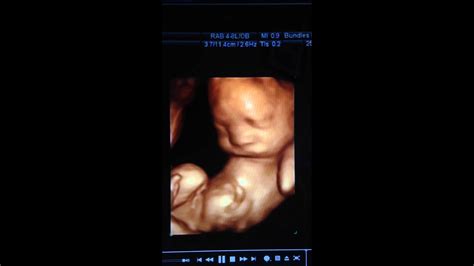

3D Sonogram At 27 Weeks – The reason that 24 to 32 weeks is the best time for getting a 3d sonogram is that by 33 weeks, your baby has descended into your pelvis, making the ability to receive clear. This type of ultrasound can make images that are clearer and more detailed than standard fetal ultrasound images. The girl ultrasound gallery is designed to show you what a baby girl looks like on ultrasound photos from various weeks of pregnancy. Babies born at 27 weeks are considered extremely premature and require a high level of care.

The image below is from a 3d fetal ultrasound. Updated may 10, 2021 image: Istock perhaps the most exciting thing about a prenatal checkup is the ultrasound —after all, it lets you see with your own eyes that the pregnancy is real, and, as your pregnancy progresses, it.

3d and 4d summary most pregnant women have an ultrasound at around 20 weeks. If you’re at 27 weeks and considering a 3d ultrasound, you’re not far off from the sweet spot! You’ll notice that what you see.